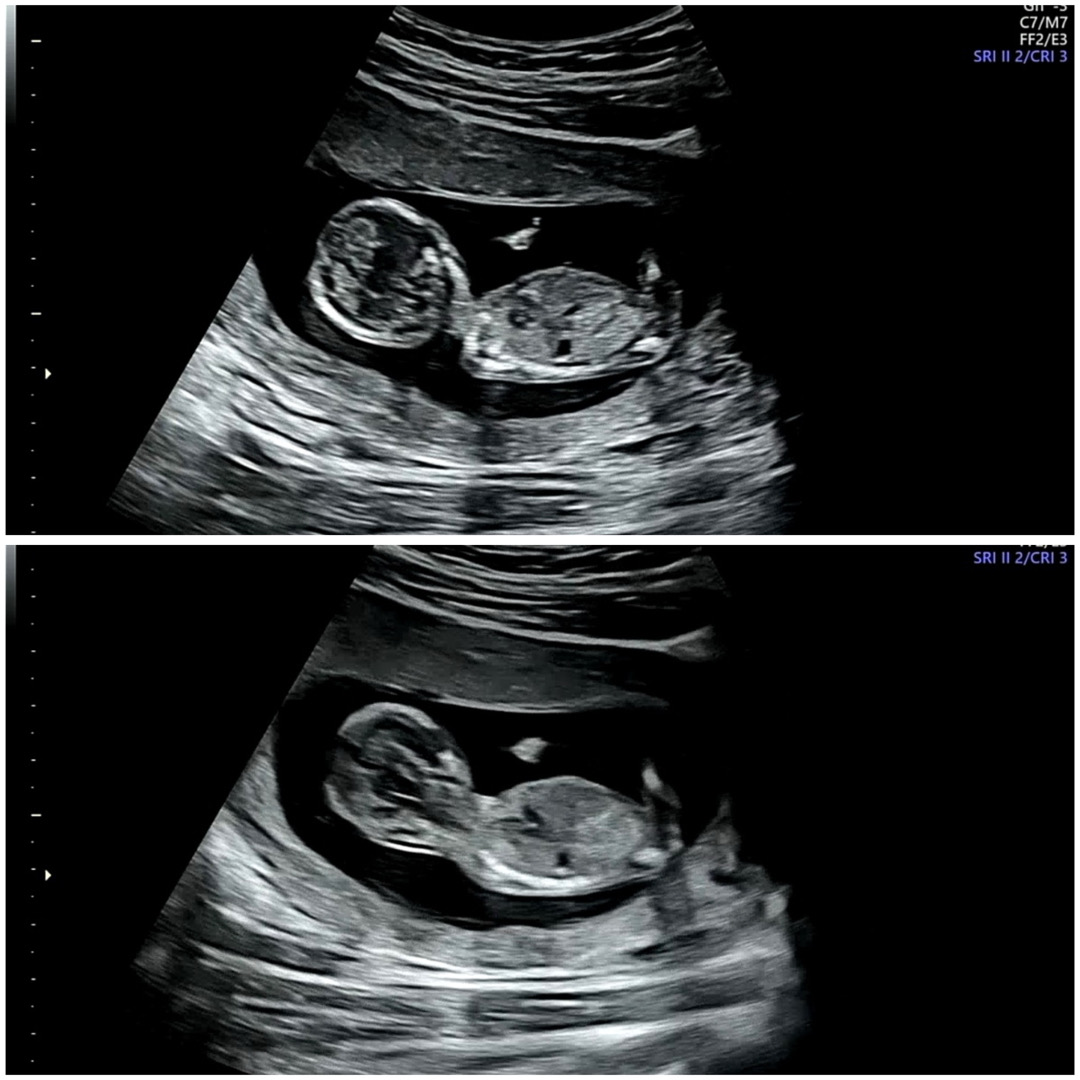

오늘 딱 13주 초음파 사진이예요 각도법 한번만 봐주세용 딸일까요 아들일까용..?